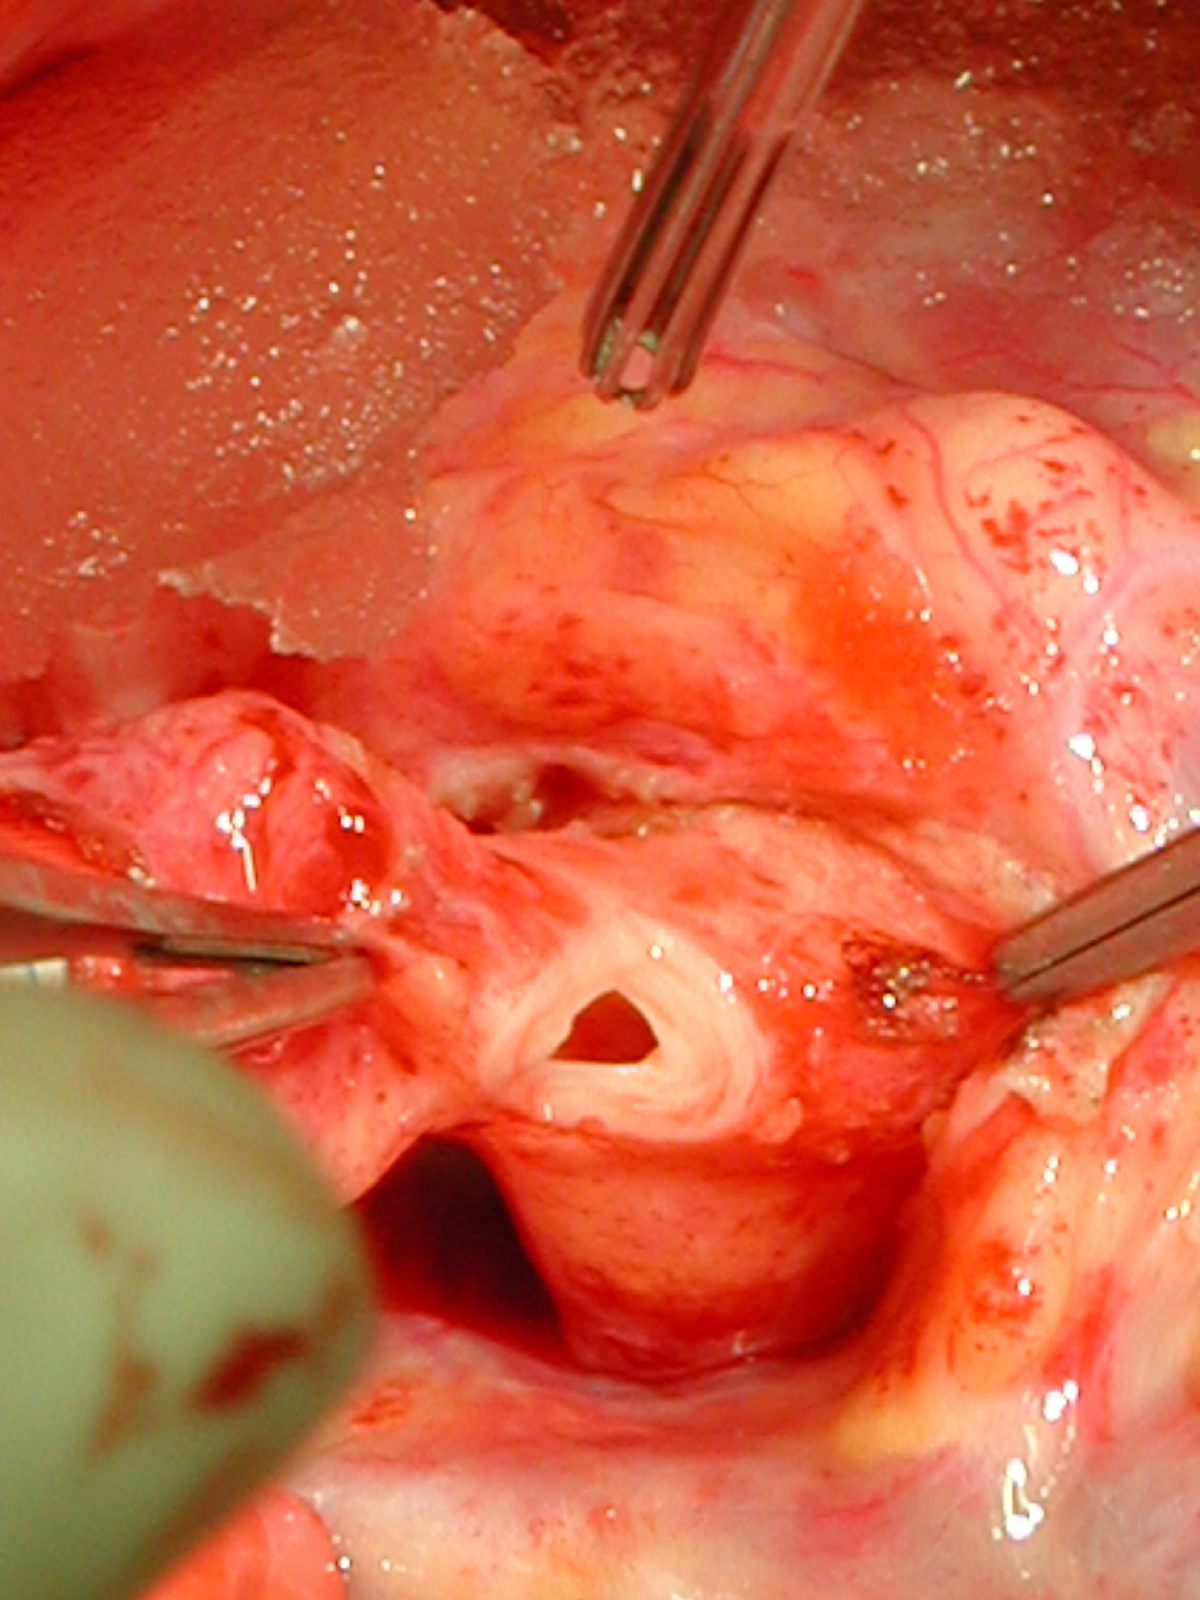

Figures 20 & 21: Third incision has been made to the right of the left coronary orifice. They yellow plastic suture boot on the pickup is pointing out the left coronary orifice. Figures 22 & 23: Proximal ascending aorta now opens widely, revealing the right and left coronary orifices and the normal trileaflet aortic valve below.

Figure Figure Figure Figure